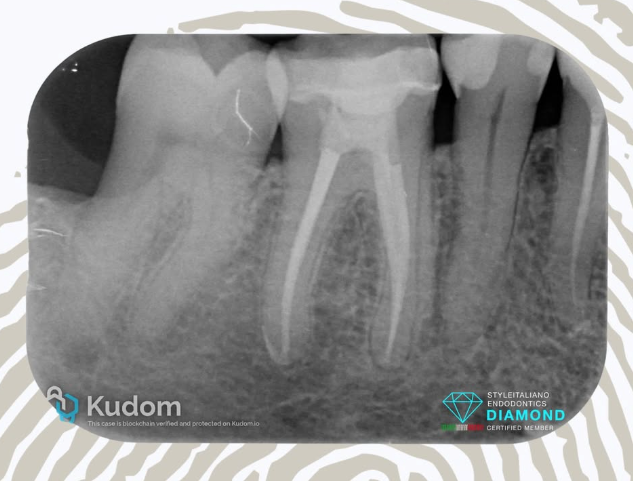

Retreatment 36 with lesion and Treatment of symptomatic 37 - 4 years follow-up.

Patient was referred for 2 problems: the tooth 36 was tender to percussion and palpation, the 37 presented the tipical signs of “Cracked tooth Syndrome” with no probing and favorable prognosis. Treatments were done in 2 visits. During the first visit teeth were shaped, cleaned and dressed with calcium hydroxide . During the second visit the canals were obturated using the Cold Hydraulic Condensation Technique, a single cone with CeraSeal bioceramic sealer. Nice recall sent by the referral Dentist after 4 years.

Case Study: Symptomatic Tooth 2.7 with Large Lesion and Sinus Tract – 4-Year Follow-Up